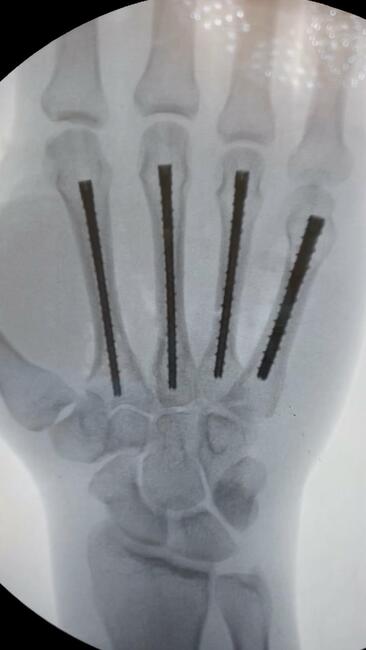

A retrograde technique was utilized for the fifth metacarpal neck and the second and third metacarpal base fractures (Video 1). An anterograde technique was used for the fourth metacarpal shaft fracture (Video 2). Following fixation, final radiographs were taken, and fluoroscopy confirmed stability with movement (Figure 2; Video 3). The hand was placed in an intrinsic plus position and a short-arm volar splint was applied. The fixation of 4 metacarpals was completed in approximately 80 minutes of tourniquet time with the splint on.

Figure 2: Postoperative radiographs of anteroposterior, oblique, and lateral views. Note the anatomic reduction with intramedullary threaded nail fixation of the second, third, fourth, and fifth metacarpals.